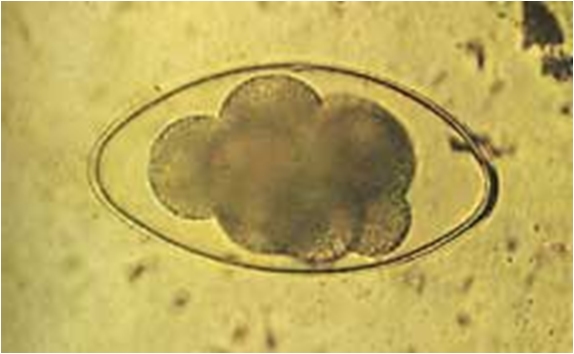

jest prosty, bez żywiciela pośredniego. Jaja z grubą

otoczką są dużo większe (250*100µm) niż te innych

Trichostrongylidae oraz niezwykle odporne na wysychanie oraz na zamarzanie

czy śnieg. Zwykle jaja zaczynają dzielić się

gwałtownie i można zaobserwować 1 do 8 ciemnych komórek.